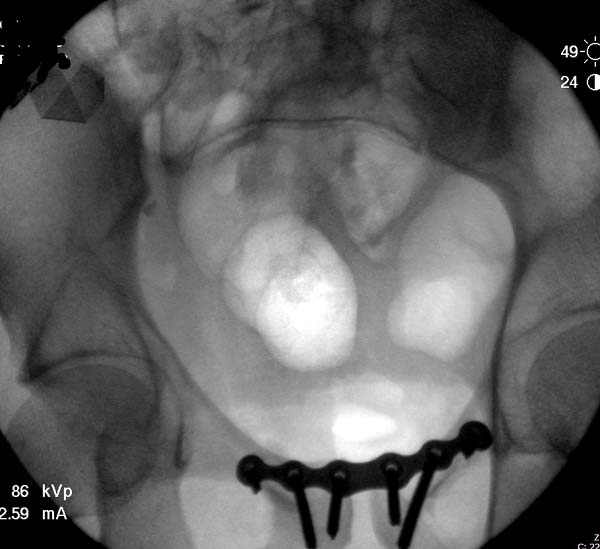

Большое спасибо всем Вам за помощь! Вчера прооперировали пациентку. Выполнили закрытую репозицию левой половины таза на тракционном столе под контролем ЭОП, закрытая фиксация левого КПС двумя каннулированными винтами. Учитывая удовлетворительное стояние отломков лонной и седалищной костей справа, а так же удовлетворительную ширину лона передние отделы стабилизировали системой ЦИТО

Послеоперационные КТ прилагаются

Винты введены в S1